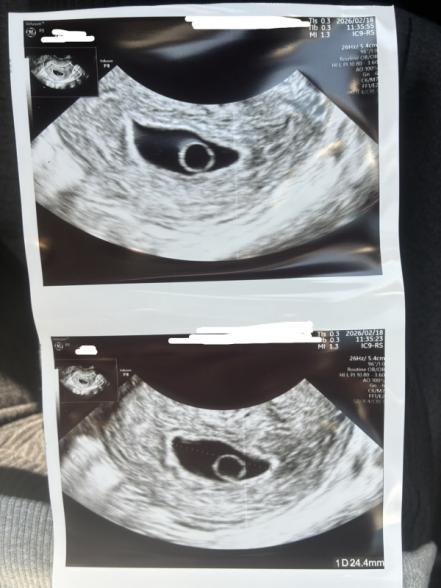

昨年12/08~12/11が最終生理日で1/24に検査薬で陽性反応が出ました。元々、多嚢胞性卵巣症候群と言われており、1人目が排卵誘発剤を飲んでからの妊娠で、産後の性行為でも特に避妊はしておらずなかなか妊娠せずでしたが、今回自然と妊娠することが出来て驚きました。ただ、排卵が大幅にズレてたそうで検診3回目までは胎嚢の少しずつの成長しか確認が出来ませんでした。4回目の検診でやっとうっすら卵黄囊が見えまして、5回目で卵黄囊がはっきり見えました。しかし、胎嚢が24.4mmなのに胎芽も見えず心拍も確認出来ずでした。

先生は、確定とは言いきれないが繋留流産の可能性が高いとのことです。1週間後、また検診することになってます。